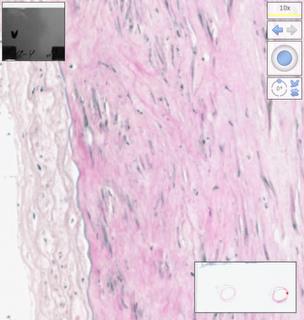

Fig. 13. Arterial homograph, 84 days of preservation in RPMI 1640 solution. Hematoxylin-eosin staining, digital magnification: single endotheliocytes with a flat pale nucleus, the basement membrane is fragmented, with areas of detachment, the intima is compacted, the inner elastic membrane in the form of fragments of different lengths and thicknesses; single myocytes, some retain contours, pale nuclei, wide areas of devastation.

Fig. 14. Arterial homograph, 84 days of preservation in RPMI 1640 solution. Weigert–Van Gieson coloring, digital magnification: intima fibers are pale, disconnected, the inner elastic membrane is in the form of a clear monoline, in the middle shell there is a light purple fibrous background of different coloring densities.